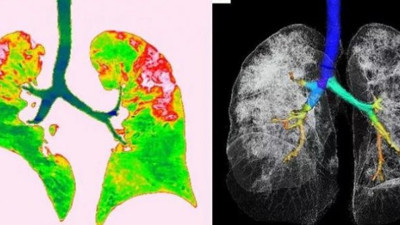

Korona virüsün akciğerlere verdiği hasar ilk defa bu kadar net görüntülendi Evrimağacı.org, korona virüsün insan ciğerine verdiği zararı gözler önüne seren fotoğrafı paylaştı.

Korona virüsün etkisi böyle görüntülendi! ABD’de bulunan George Washington Üniversitesi Hastanesi’ndeki doktorlar, korona virüs (Covid-19) hastasının akciğerlerini 360 derece sanal gerçeklik teknolojisi kullanarak görüntüledi. Sanal gerçeklik görüntüsünde, korona virüsün akciğerlerde yayılması ve verdiği hasar görüldü.